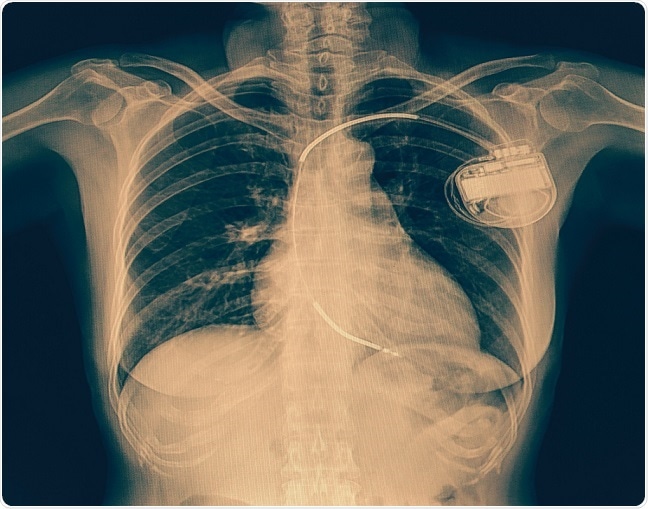

Currently, the main therapy for children at risk of sudden cardiac death is the surgical implantation of a cardioverter defibrillator. However, this involves invasive surgery and prolonged hospitalization, when in many cases, young patients only need a temporary “bridge” to help their heart. They may be waiting for a heart transplant, for example, or be recovering cardiac function after having been newly diagnosed with heart failure. In instances such as these, patients would not be good candidates for surgically implanted devices, explains Spar.

© Kasa1982/Shutterstock.com

In 2015, wearable cardioverter defibrillators were approved by the by the U.S. Food and Drug Administration for use in pediatric patients. However, there has been limited information about their safety and efficacy in children. If effective, the devices could prevent the need for prolonged hospitalizations, while still protecting against dangerous arrhythmias.